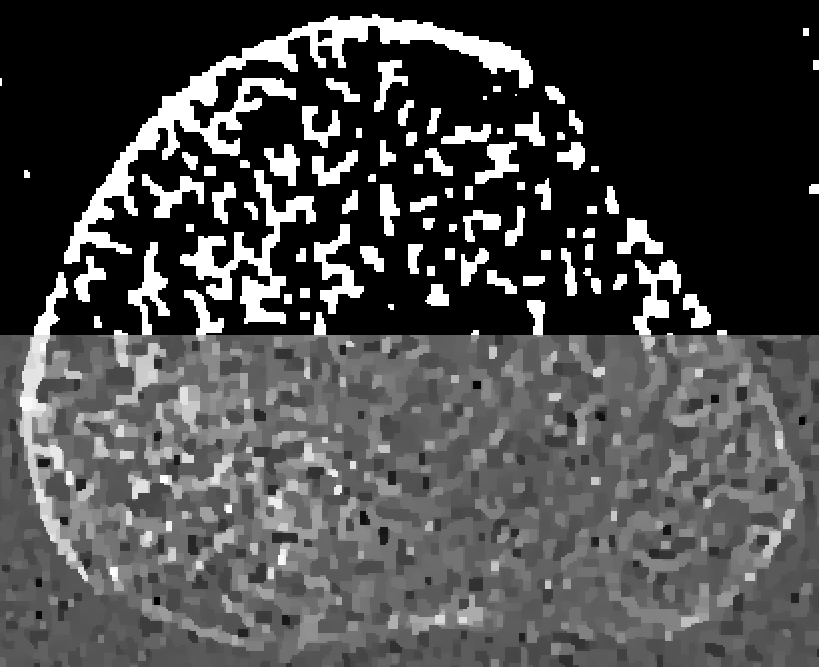

Refer to captionID blurfullRefer to captionshort-1Refer to captionshort-2Refer to captionSI blurRefer to captionRefer to captionRefer to captionSV blurRefer to captionRefer to caption0.0000.0150.0300.0450.060

Figure 4: Reconstructions of the medial bone with the highest mutual overlap over all thresholds and β𝛽\beta’s. The top half of each reconstruction is thresholded.

Figure 4 shows the medial-bone reconstructions (bottom of each image) and segmentations (top of each image) corresponding to the best possible mutual overlap (optimal threshold and β𝛽\beta values) with each scan type and blur model combination. All SV reconstructions depict more trabecular structure than the shift-invariant (SI) or ID models. The difference in image quality among ID reconstructions is readily apparent in these images, with the short-1 scan resulting in the most trabecular detail. Finally, the SI images depict more detail than the ID model but less detail than the SV reconstructions. However, the SI model results in a ringing artifact, particularly evident on the lower left aspect of the medial bone in the full scan reconstruction. This is likely due to blur/model mismatch (the SI model is accurate at the center of the detector but less accurate at the edges).